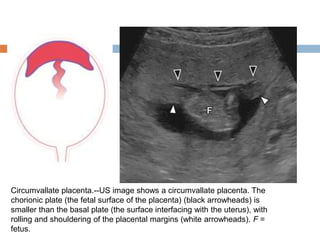

Circumvallate placenta.--US image shows a circumvallate placenta. The

chorionic plate (the fetal surface of the placenta) (black arrowheads) is

smaller than the basal plate (the surface interfacing with the uterus), with

rolling and shouldering of the placental margins (white arrowheads). F =

fetus.

Circumvallate placenta.--US imageshows a circumvallate placenta. The chorionic plate (the fetal surface of the placenta) (black arrowheads) is smaller than the basal plate (the surface interfacing with the uterus), with rolling and shouldering of the placental margins (white arrowheads). F = fetus.